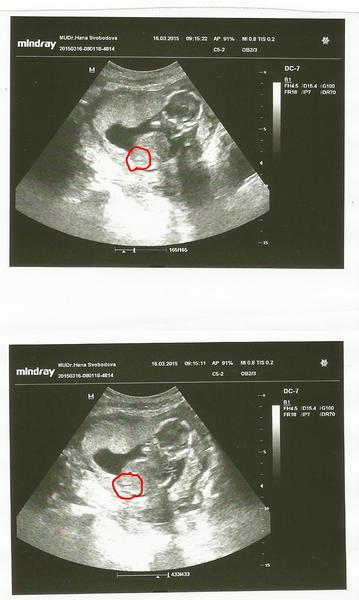

Ahoj maminky a budoucí maminky 😉 Prosím, poradila byste mi některá, co vidíte na fotce z ultrazvuku ve 20. týdnu za pohlaví? Určitě jste foteček viděly už mraky, proto vás žádám o radu...Nechci nikoho ovlivnit, proto svůj tip řeknu později 🙂 Děkuju moc!!!

ja teda vidim jasnyho pindika 😀 na pupecnik mi to prijde dost nizko..

Teda moc dekuji za názory paní doktorka nám tvrdí holčička,ze tam nic nevidí nic nenarostlo to jsem tedy napjatá :*